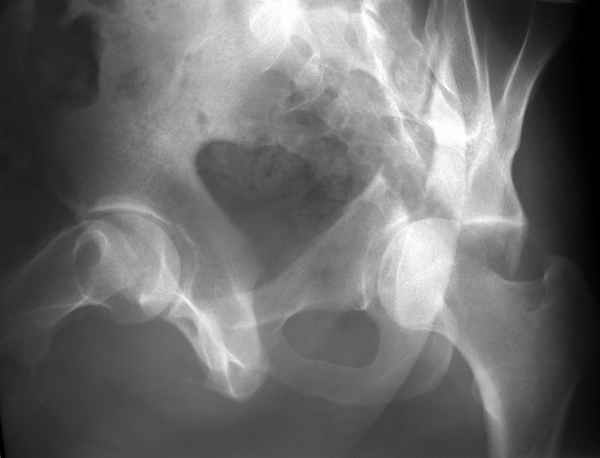

Конечно изнутри таза массивная гиперпластическая мозоль - пришлось немного попотеть и интерпозиция по плоскости перелома. Хорошо был виден ствол нерва с внутренней стороны вырезки - сделали блокаду, как положено. После операции движения стопы в полном объеме чувствительных расстройств нет. Репозиция удалась - мы были в легкой эйфории - внесуставной доступ и т.д. Через сутки стопа повисла - грубых выпадений на ЭНМГ нет, но тем не менее ишемический неврит малоберцовой порции седалищного нерва - бич застарелых повреждений.

Ах если бы Русские люди не обманывали себя и больных, а направляли бы срочно в специализированные отделения, то можно было бы получить хороший результат куда меньшей кровью пациентов и сердечных ран хирургов. Посылаю еще два снимка. Привет ЛАФ.